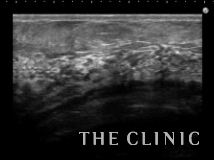

除去した壊死脂肪と術後10日目のエコーです。

しこりは完全に消失しています。